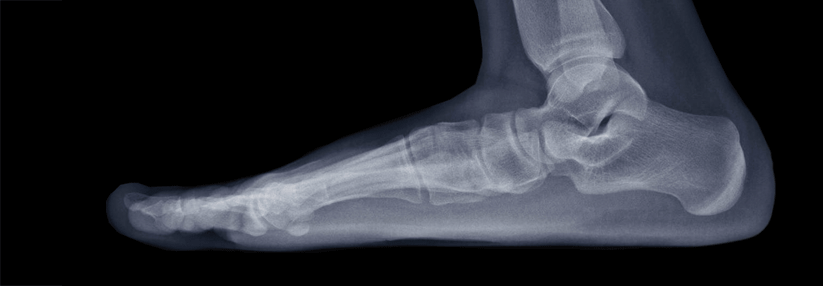

Wenn Fußschmerz den Spaziergang vergällt, ist medizinische Hilfe gefragt. Die Diagnose Plattfuß gelingt meist in wenigen Minuten – ganz ohne…